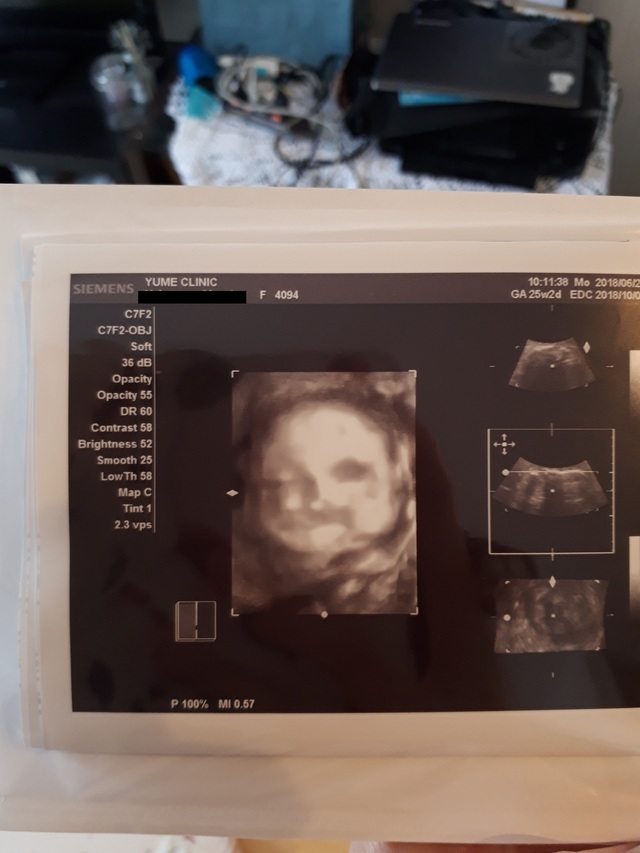

25週0日(25w0d・男の子)|まぁりん さん(31歳)

エコー写真撮影時のエピソード:

初めて顔の様子がハッキリわかった4Dエコーです!それまでなかなか4Dエコーをしてもらえず、ずっと顔が見たいと思っていました。里帰り先の産婦人科で撮っていただいたものです。旦那もこのエコー写真を見てとても喜んでいました。

私は4回の流産を経てやっとここまできたので、エコー写真をもらうたびにうれしくてたまりません!これからも大切に育てていきます。大きくなぁれ!